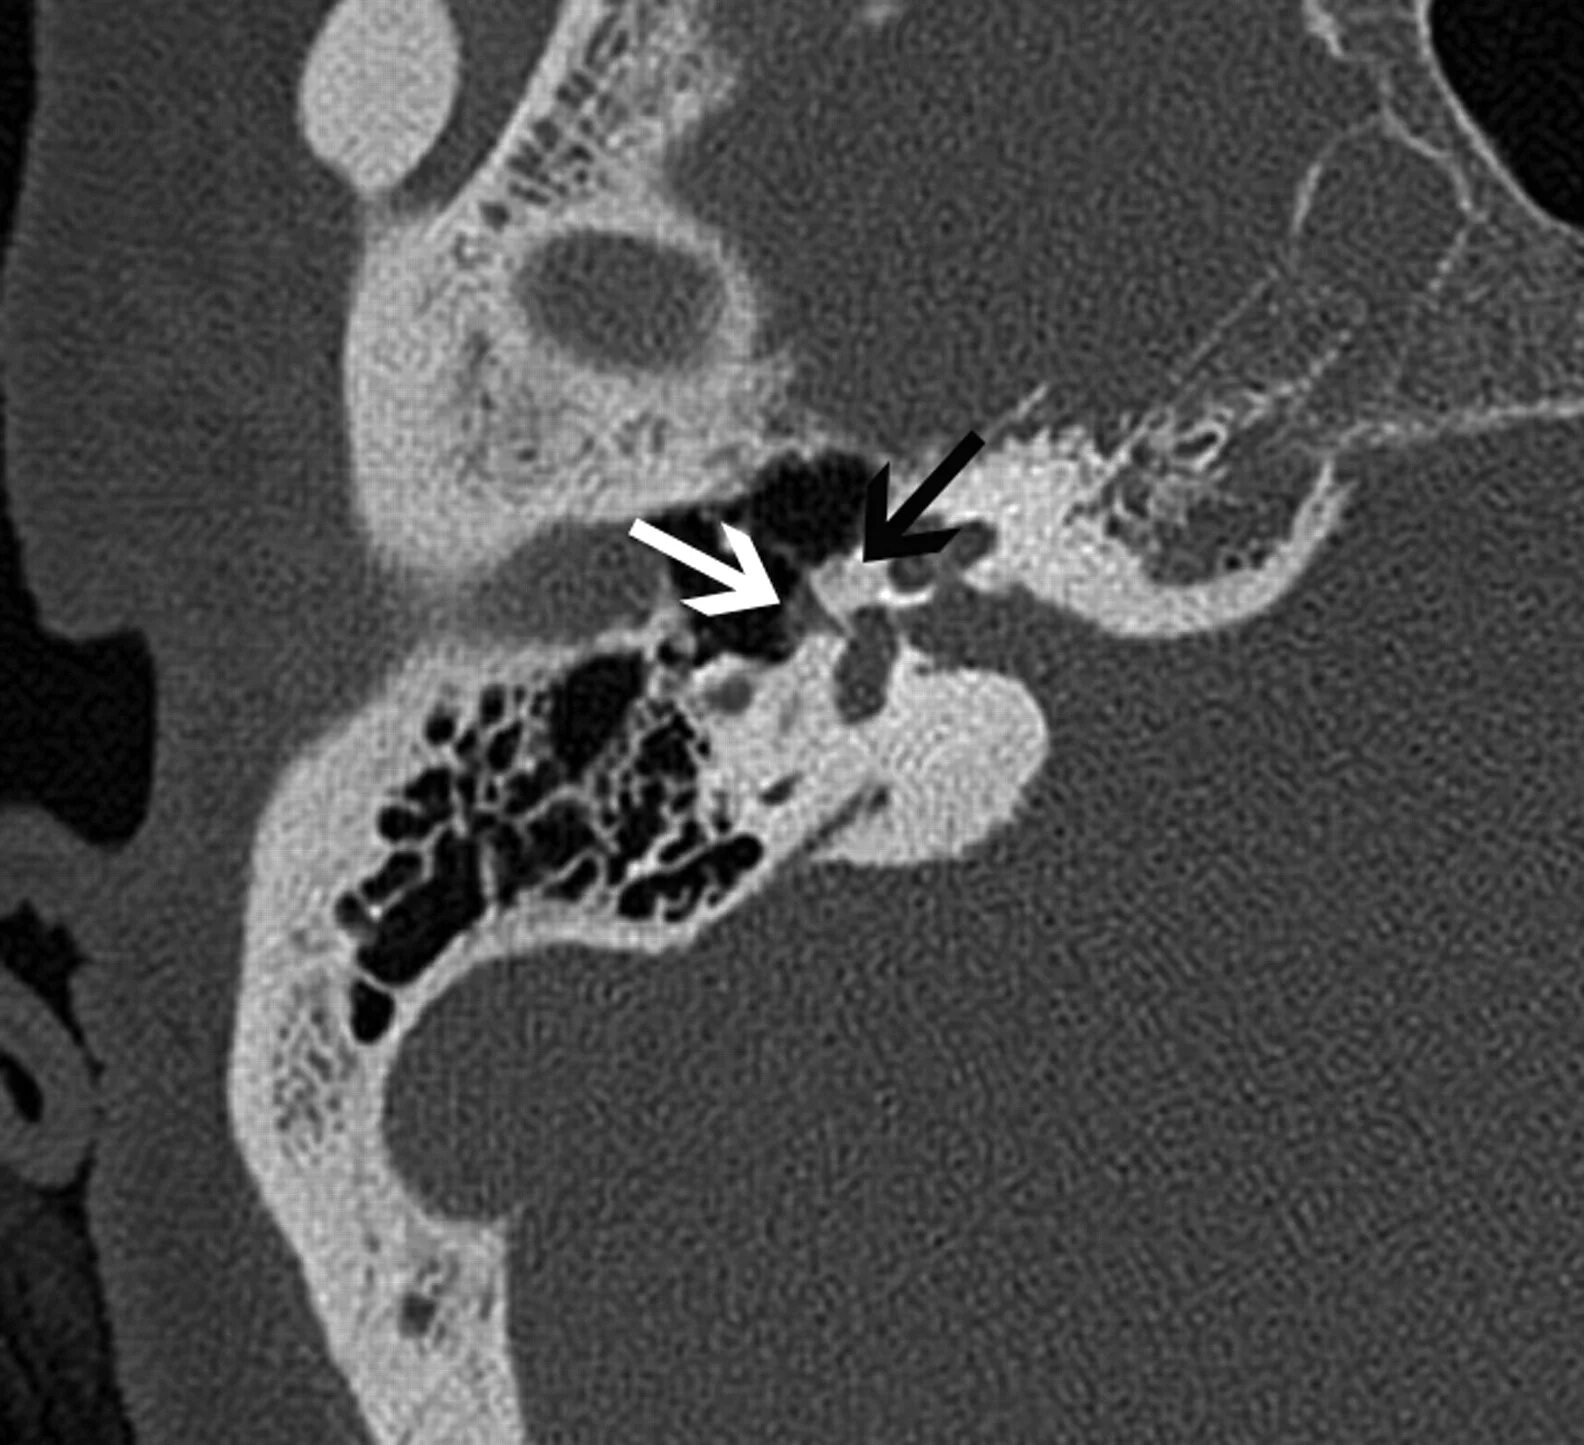

Кохлеарный отосклероз